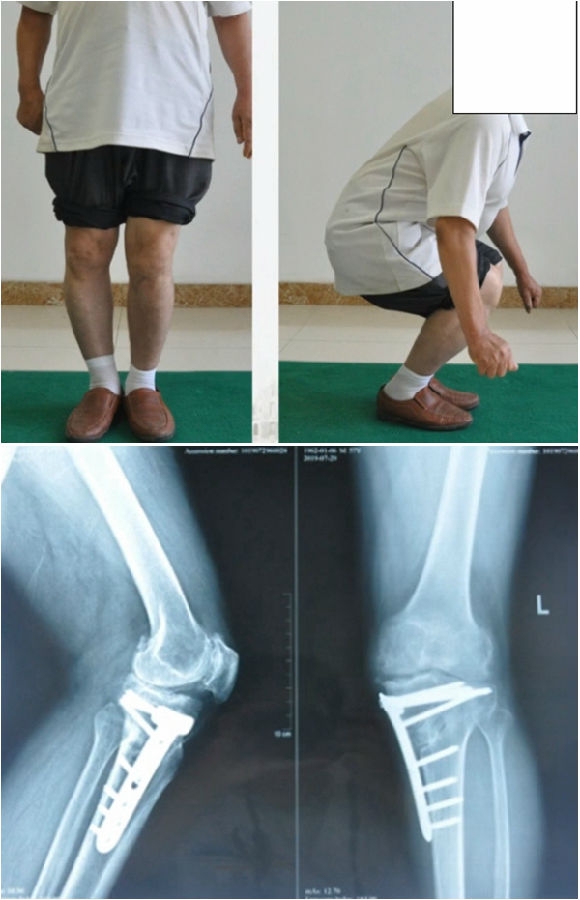

典型病例,男性,65岁,农民,双膝内翻16度。

术前影像

第一次为该患者做了传统上行开放截骨,撑开角度较大,术后用三种方法测量髌骨高度,发现髌骨高度受到影响,髌骨变低了。

左膝上行OWHTO(初次)

上行OWHTO髌骨高度测量

ISI法测量髌骨无明显变化;CDIBPI法测量髌骨降低明显;患者屈膝锻炼困难。

第二次来院做另一侧肢体时,采用下行截骨,术后患者髌骨高度,无论用哪种方法测量都无明显变化,而且患者膝关节功能迅速得到恢复。

右膝下行OWHTO(再次)

下行OWHTO髌骨高度测量

ISI法测量髌骨无明显变化;CDIBPI法测量髌骨无明显变化;患者屈膝明显改善。